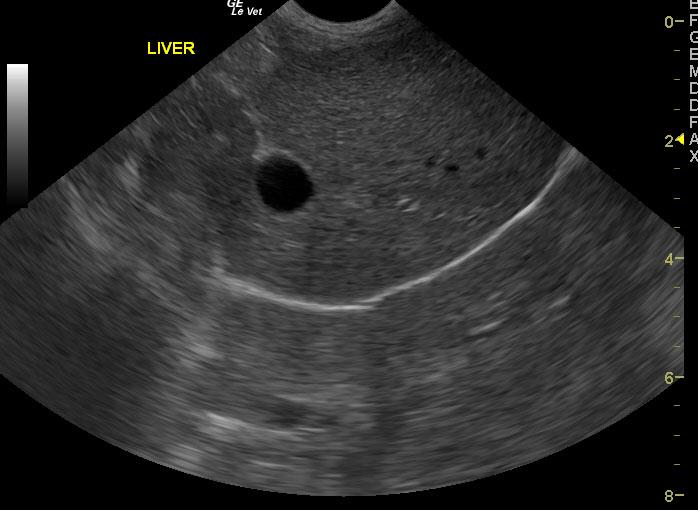

Exam of the cranial abdomen demonstrated normal liver size, contour, and structure. Parenchymal echogenicity was naturally coarse and hypoechoic to the spleen. Vascular and biliary tracts were of normal volume and no evidence of congestion was noted. The portal vein, caudal vena cava, and aorta were 0.6/0.56/0.6cm respectively revealing a PV:CVC and PV:Ao ratio of 1:1 ruling out the presence of extrahepatic shunts. The urinary bladder, trigone and pelvic urethra presented normal wall thicknesses with anechoic urine and normal tone. No uroliths or sediment were visualized.